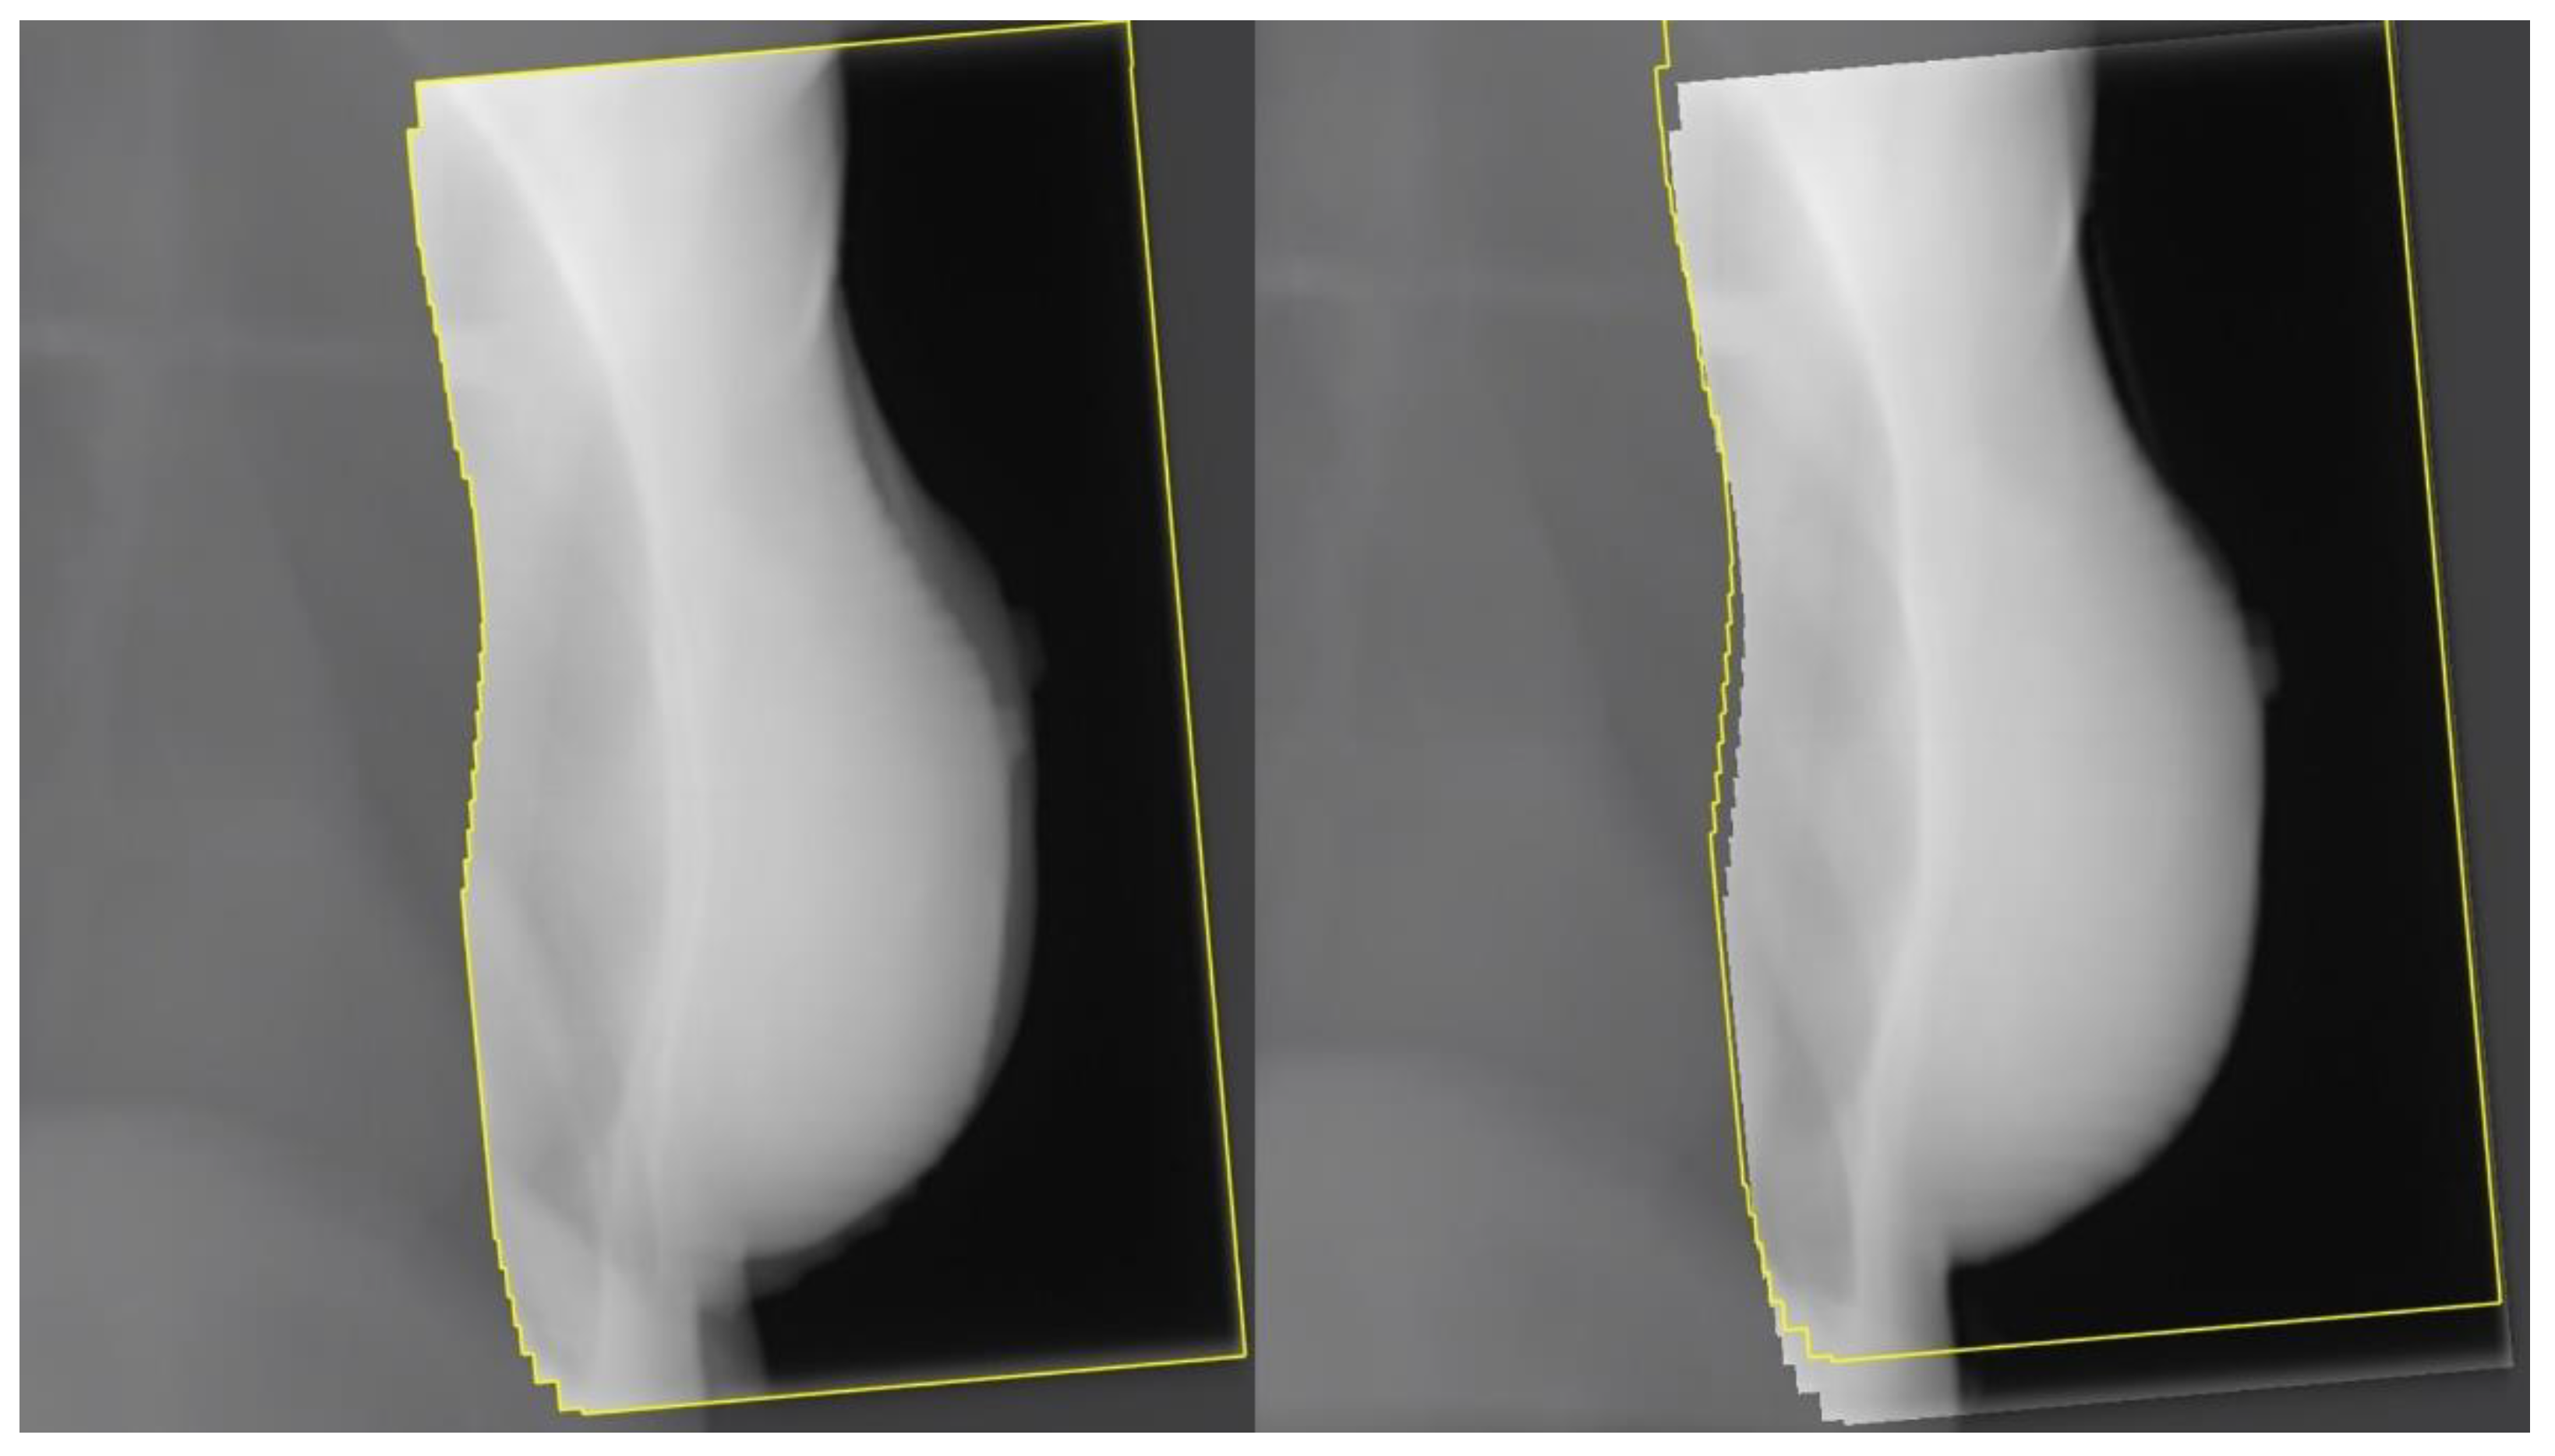

Figure 2. 2D Megavoltage Electronic Portal Imaging (EPID) as a daily IGRT online setup of a breast carcinoma radiotherapy: before (left) and after (right) alignment.

The progress in radiotherapy is based mostly on the use of new technologies. Currently. external beam radiation is performed using linear accelerators after computed tomography-based imaging (Figure 1) and 3-dimensional planning using sophisticated technologies, including intensity-modulated radiation therapy (IMRT). The control of the accuracy of the dose delivery can be increased with image-guided radiation therapy (IGRT, Figure 2). The dose to the heart can be substantially decreased by delivering radiation in deep inspiration (Figure 3) or prone position [4,5].